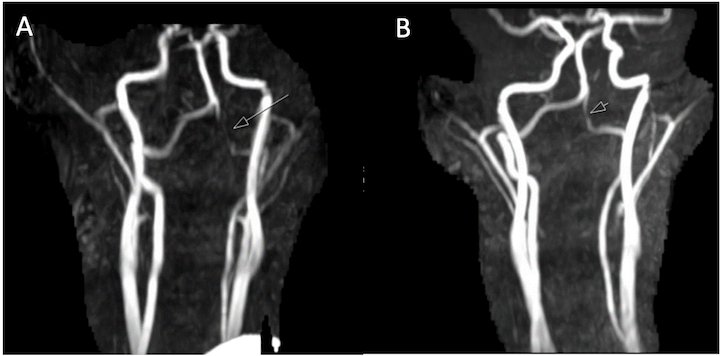

CTA demonstrated subtle narrowing of the left vertebral artery (VA) at the atlantooccipital joint with asymmetry in the position of the dens relative to the lateral masses of C1, raising concern for dynamic vessel compression. TCD with and without neck rotation and flexion/extension radiographs of the cervical spine were non-diagnostic. Given ongoing concern for rotational vasculopathy, the patient was started on aspirin 81 mg and was placed in a soft cervical collar with plans for further imaging once he had recovered from his acute stroke. Eight weeks later, he underwent contrast-enhanced MRI/MRA of the head and neck with dynamic positioning, which re-demonstrated left VA narrowing at the occipital condyle-axis joint with focal narrowing when piercing the dura. MRA in 8 positions demonstrated loss of flow-related enhancement with left head tilt and neck extension. A new area of T2 hyperintensity was visualized on MRI in the left cerebellum, likely representing an interval infarction. He subsequently underwent a C1 laminectomy without complication fourteen weeks after his initial presentation.

Since his procedure, he remained asymptomatic without recurrent episodes of dizziness or gait instability. Repeat MRI/MRA 6 months after his operation showed improved caliber of the left V3-V4 segment and preserved flow related enhancement in the V4 segment. Dynamic contrasted-enhanced MRA imaging can serve as a non-invasive alternative to DSA in the diagnosis of rotational VA syndrome and should be considered in suspected cases of pediatric rotational arteriopathy.